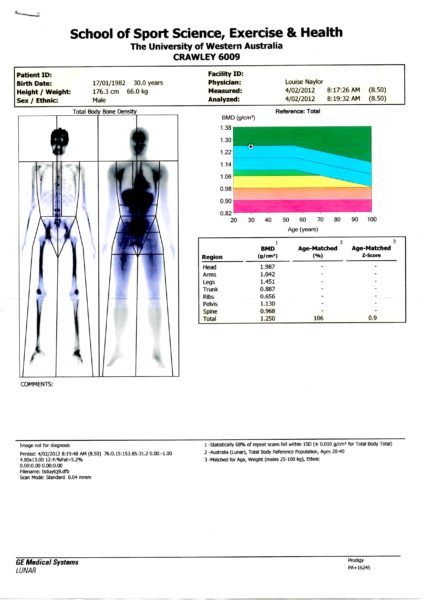

Le DEXA, initialement développée dans les années 80 pour la mesure du contenu minéral osseux, s’est imposée comme la méthode de référence pour l’étude de la composition corporelle. Elle consiste à balayer l’ensemble du corps avec un faisceau de rayons X à deux niveaux d’énergie. Le rapport des atténuations de ces deux rayonnements est fonction de la composition de la matière traversée. L’irradiation imposée au patient est faible et similaire à celle correspondant à une radiographie pulmonaire. La calibration est effectuée avec des fantômes artificiels contenant des triglycérides et du calcium. Le DEXA permet de séparer trois compartiments (masse grasse, masse maigre et contenu minéral osseux) par un traitement informatique des mesures physiques. La précision est excellente. le DEXA mesure la valeur du compartiment osseux, négligé jusque-là. Le balayage du corps entier et le traitement d’images permettent une approche régionale (bras, tronc, jambes) des trois compartiments mesurés, impossible à réaliser avec les autres méthodes. J’ai eu l’occasion d’en refaire un en Australie lorsque je m’entraînais avec l’Unviersity Western Australia avant mon accident.

On a donc évalué sur une semaine complète quelles étaient mes dépenses et recettes énergétiques. En clair, je notais et pesais tout ce que je mangeais et buvais sur une semaine complète. De l’autre côté de la balance, je consignais tous mes entraînements et courbes d’analyses de fréquence cardiaque. Nathalie avait calculé à l’époque que je dépensais autour des 7000 calories par jour, mais que mon alimentation malgré les nombreuses collations n’apportaient que 6000 calories. Il a fallu établir un programme nutritionnel adapté à ma pratique. Le DEXA avait également montré que, quand bien même mon contenu minéral osseux était dans la norme, il était dans la limite basse. Ceci est un indice annonciateur d’un surentraînement qui pourrait engendrer une fracture de fatigue. Deux endroits sont analysés par la machine, le col du fémur et le bas du dos.